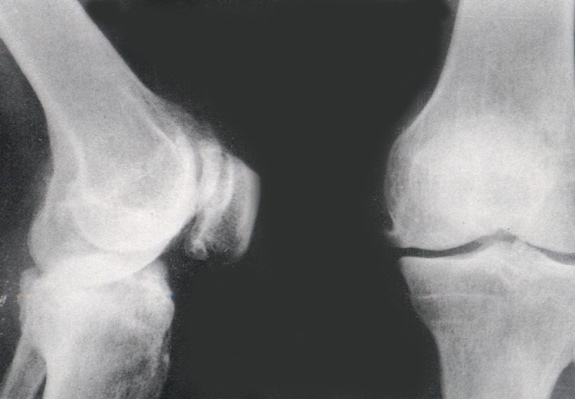

骨质疏松是正常骨骼的骨密度与骨质量下降,而骨质增生是正常骨骼以外新生的骨赘。骨质疏松的本质是指骨骼的骨量减少,骨的微细结构破坏,骨生物力学性能下降;在显微镜下可见骨小梁稀疏、变细、消失,表现为骨骼内部质和量的病变。这两种病变可以出现在同一处关节,就像一个"烂了心"的萝卜表皮上有几个小突起,萝卜心代表骨质疏松,而萝卜上的突起就代表骨质增生或骨赘。

骨质增生主要发病部位是活动较多且负重较大的关节,如颈椎、腰椎、膝关节等关节周围会有不同程度的骨质增生;不是所有的骨质增生都引起骨关节疼痛,轻时外观亦无异常;如果骨质增生增大而刺激了骨膜或神经,则表现为关节活动时疼痛,休息后疼痛可逐步好转、消失。病情反复发作加重后,会出现关节红肿、积液,甚至关节变形,疼痛程度不断加重,关节活动逐步受限。可以说,骨性关节炎的疼痛与关节负重运动、气候温度变化关系密切。